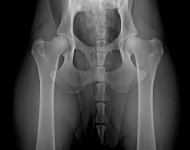

(1) 7 týdnů VD

(1) typ 3

(3) 7 měsíců VD 1

(3) typ 3 po korekci polohy pánve

(4) 7 měsíců VD 2

(4) typ 3 po korekci polohy pánve 2

Americký stafordširský teriér (VD)

DKK 2a